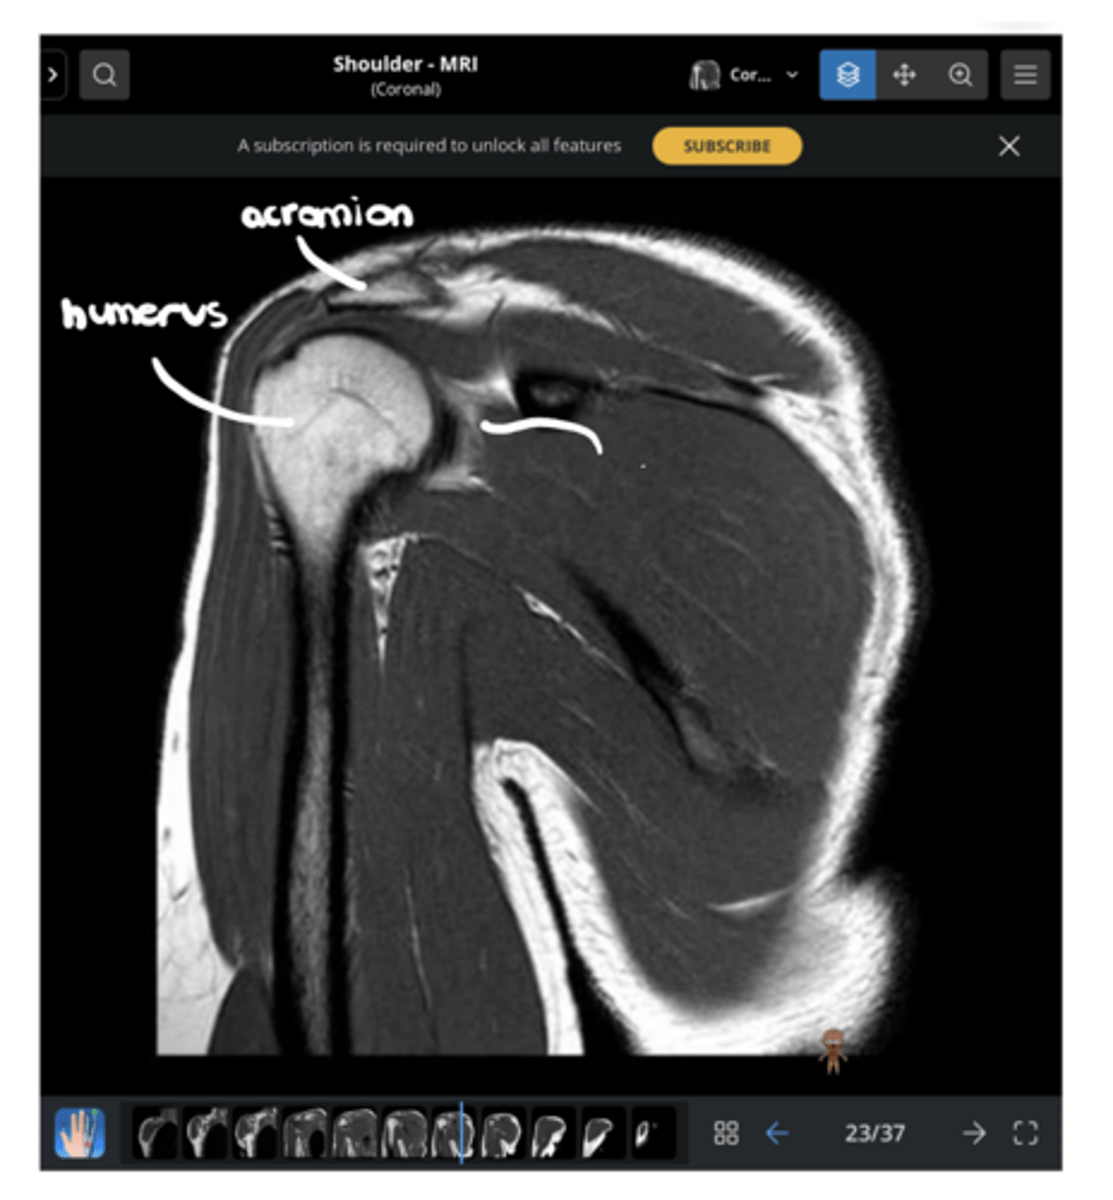

Anterior coronal view of the shoulder -- key to setting this image up is finding the coracoid process, which is NOT present on the back side

What type of view is this? Anterior vs. posterior? How do you know?

1. Anterior

2. Coracoid

1. What view is this image?

2. Which structure is being pointed to?

1. Lateral deltoid

2. Acromion

3. Clavicle

4. Supraspinatus footprint

5. Glenoid

Working our way around clockwise, which structures are being pointed to?